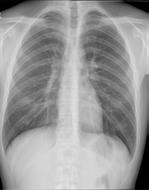

40.000 röntgenopnames borstkas 30.000 algemene röntgenopnames 20.000 MRI scans 34.700 CT-scans 10.600 echografiëen 5.000 mammografieën 15% andere 24% röntgenopnames borstkas 18% algemene röntgenopnames 21% CT-scans 12% MRI scans 7% echografiëen 3% mammografieën

In het UZA gebeuren op de dienst medische beeldvorming elk jaar meer dan 165.000 radiologische verrichtingen. De röntgenstralen en hun slimmere broertje de CT-scan vormen het grootste deel.